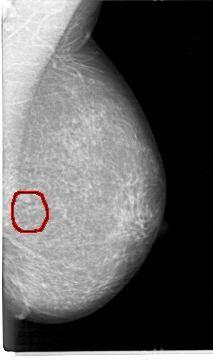

D_4026_1.LEFT_MLO

LEFT_CC LINES 5386 PIXELS_PER_LINE 3106 BITS_PER_PIXEL 12 RESOLUTION 43.5 OVERLAY

FILE: D_4026_1.LEFT_CC.OVERLAY

TOTAL_ABNORMALITIES 1

ABNORMALITY 1

LESION_TYPE MASS SHAPE OVAL MARGINS OBSCURED

ASSESSMENT 0

SUBTLETY 3

PATHOLOGY BENIGN

TOTAL_OUTLINES 1

BOUNDARY